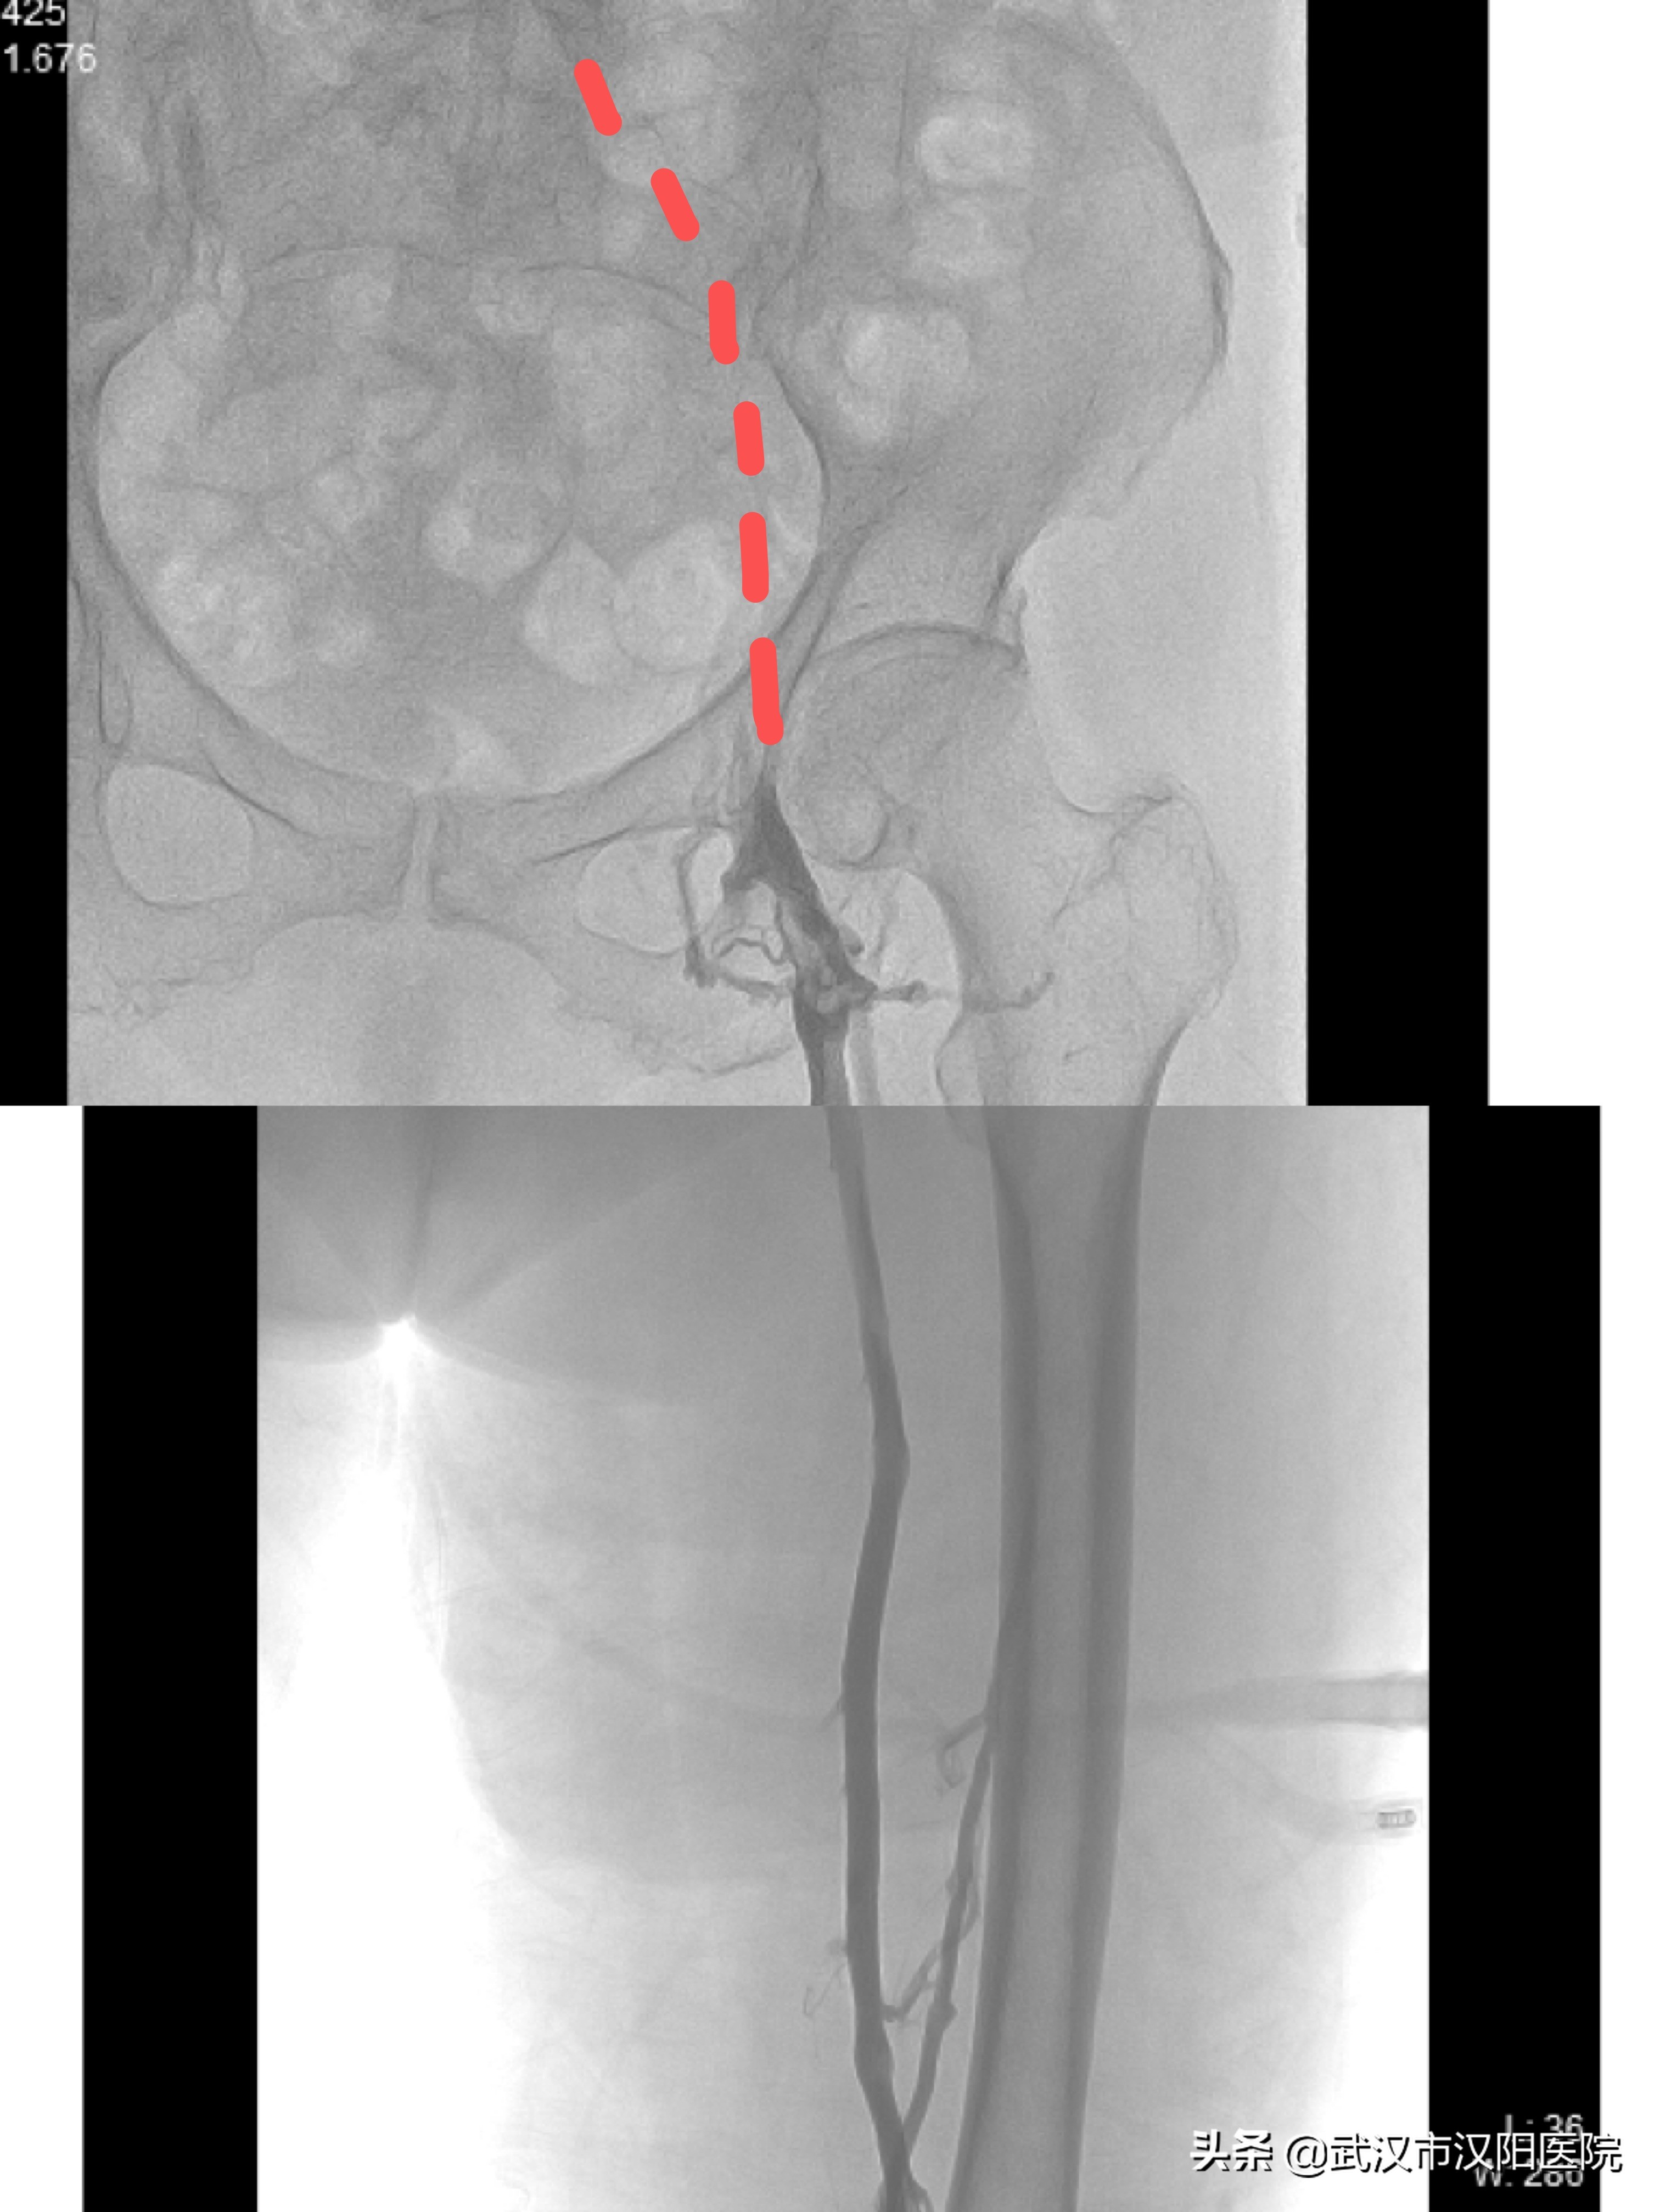

图2:抗凝一周后股腘静脉显影,髂静脉未显影

进一步完善相关检查后,血管外科赵红主任再次与其女儿沟通,家属表示想积极治疗,达到更好的治疗效果。赵红主任与总住院医师廖润格再次评估手术风险后决定,立即实施微创介入手术。术前充分评估并制定了详细手术方案及预防措施,降低其出现并发症的风险,于是又为她安排了微创的下肢静脉血栓的机械性清除术和髂静脉支架术。这种微创的血栓抽吸术在局麻下完成,无任何切口,病人平卧于DSA床上,仅在小腿后方有一针眼大的穿刺点,这种微创手术出血少、无创、无切口,可不受年龄限制,只要病人可以平卧都可以耐受手术。

手术中仅花费280秒即完成微创的血栓抽吸治疗,股腘静脉基本恢复通畅,但髂静脉明显狭窄,导致病人左下肢还有肿胀症状,又用半小时行髂静脉球囊扩张支架植入术,卢奶奶在手术台上左下肢就明显松软了,手术过程十分顺利。仅仅入导管室不到1小时,出来后她的腿就明显消肿了。